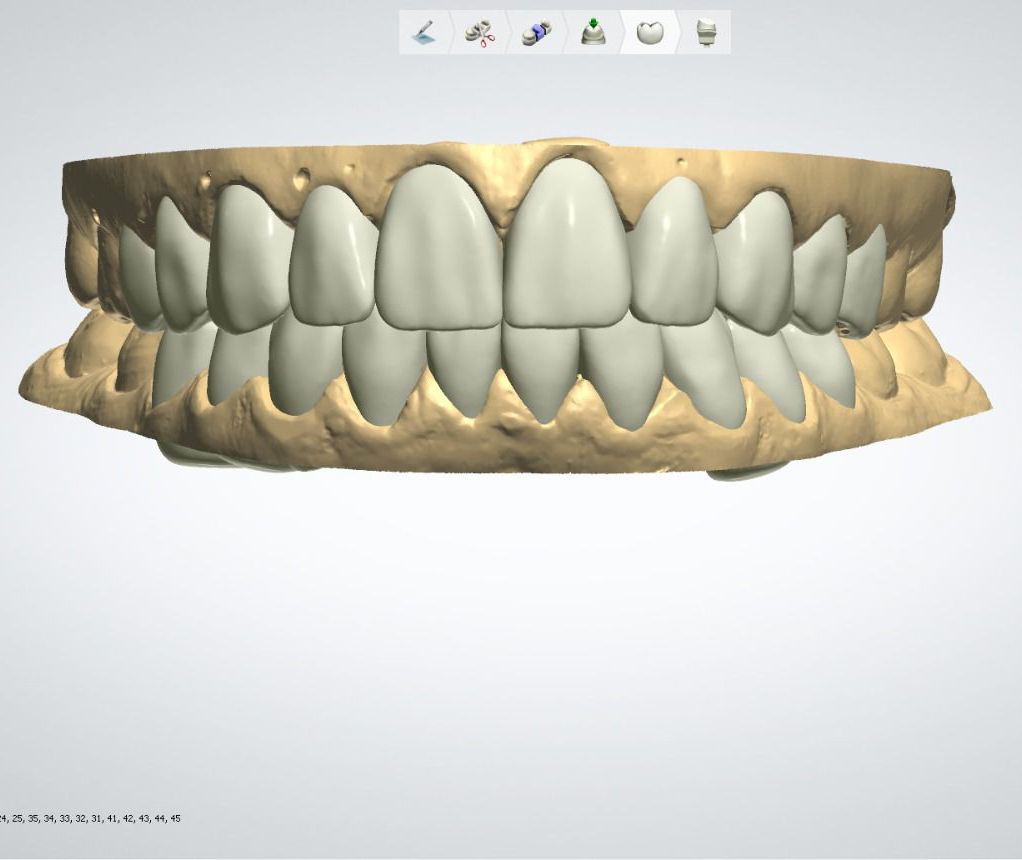

Casos de éxito

Estos son algunos de nuestros casos de éxito, mostrando el antes y después de nuestras intervenciones.

Diseño de carillas de premolar a premolar, tanto superior como inferior.